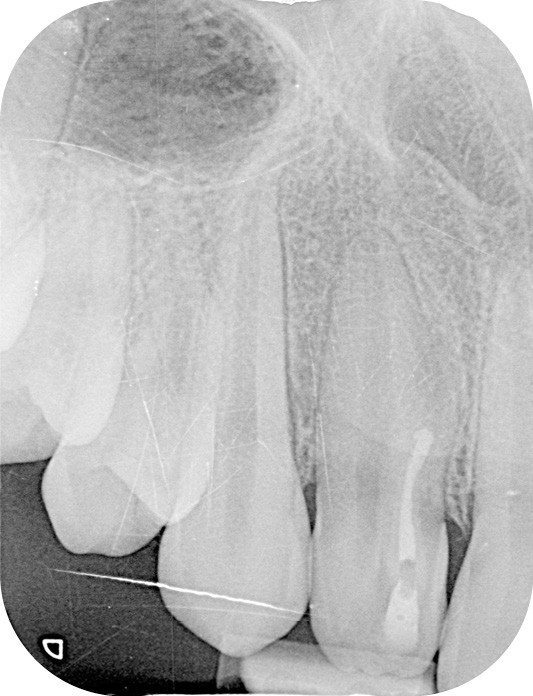

La patiente, âgée de 12 ans, s’est présentée à ma consultation avec une demande du chirurgien de réaliser le traitement endodontique de la 12 avant le curetage sous anesthésie générale. La radiographie périapicale préopératoire a mis en évidence une anatomie complexe. Les tests préopératoires ont montré un sondage parodontal sain, une percussion positive et un test au froid positif. La patiente présentait également une fistule vestibulaire active. Le Cone Beam a mis en évidence la présence d’une dens in dente et d’une lésion imposante ainsi qu’une palatoversion importante de la racine de la 12. La lésion est-elle responsable de ce mouvement dentaire ? (fig. 1, 2 et 3).

Le contrôle clinique à un mois m’a permis d’apprécier une cicatrisation complète de la fistule, augurant une future cicatrisation osseuse (fig. 7). Cette cicatrisation a pu être objectivée radiographiquement lors du contrôle à 6 mois (fig. 8), du contrôle à 1 an (fig. 9) et sur le Cone Beam à 1 an (fig. 10).

Il est également intéressant de constater le mouvement naturel de la dent sur l’arcade, qui sera tout de même traitée par orthodontie prochainement. Ce mouvement est-il la conséquence de la cicatrisation de cette lésion importante ?